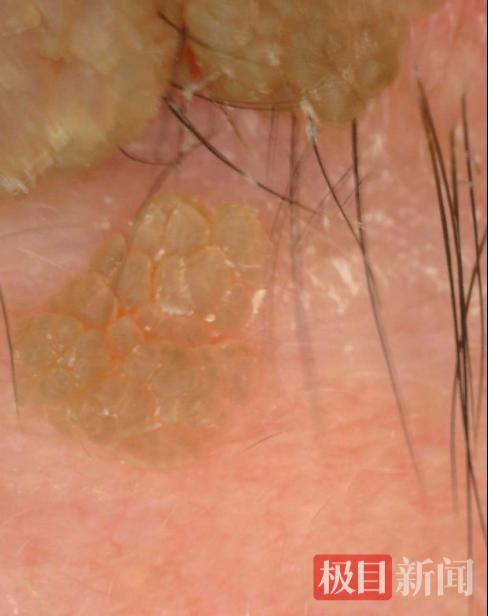

近日,丁先生来到武汉市皮肤病防治院光谷院区就诊。皮肤内二科副主任医师张成国接诊后,经专科检查及皮肤镜影像,确诊其右下眼睑外侧3颗深褐色乳头状赘生物为寻常疣,最大疣体直径达1.0cm,已明显压迫眼睑边缘,严重影响正常生活。考虑到疣体位置特殊、体积较大,若采用冷冻或激光治疗易损伤眼睑精细结构,可能引发疤痕挛缩或眼睑外翻等并发症,于是张医生给出不同的治疗方案,经充分沟通病情与治疗利弊后,丁先生最终选择手术切除,力求彻底祛除疣体、降低并发症风险。